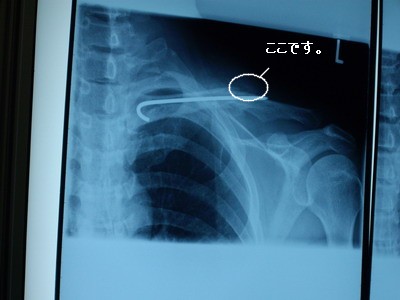

我が家のおいやん(旦那)。

2月22日に手術を受けてから、一体どれだけの時間が経ったのか・・・。

術後何回か病院に通って診察してもらってたんですが

これといった進展もなくただ毎日毎日

『イタイイタイ』

と、聞くのがウザイくらい言ってました。

って期待してたんやけどこれがどうしたもんだか・・・

骨が微妙・・・

ドクターいわく再生されてる骨は

「ここらへん。」

・・・らしいです。

病院から帰って来たおいやんに骨の再生は微妙と

聞いたくりやは即効でこう聞きました。

「その骨の回復能力は年相応??」

ほしたらおいやんは

「ちゃう!ワシの折れ方は骨折王子(息子)と違うんやて!

あいつのんは、ウインナーで言うたら中身だけ折れた状態や。

ワシのんは、骨膜っちゅう外側の膜が破れてんねん!

医者もそういうてたやろ!!」

今回レントゲンを見て思ってのが

やっぱり手術はやって正解だったと言うとこでしょうか。

この状態で固定のバンドだけだったらほぼ、動けてない状態だったんじゃないかと

思います。

ナイス助言をくれたお方にはほんとに感謝ですよ。

なにも分からずだとバンドで延々と不自由な生活を送ってたんじゃないかと思います。

ほんまに鎖骨骨折をなめたらあかんと思いました。